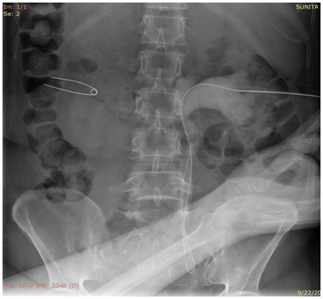

Precise point of entry was confirmed by a performing a nephrostogram and once the access into target calyx was confirmed the needle was exchanged over 0.035 Terumo guide wire. The tract was serially dilated, catheter introduced and guide removed after confirming correct placement of catheter tip. The nephrostomy tube was secured and urobag attached. Post procedure nephrostogram was performed Figure 2.

Figure 2a Radiograph showing the puncture needle in the dilated opacified PCS.

Figure 2b Radiograph showing the guidewire in the opacified PCS and the ureter with the needle in the PCS.

Figure 2c Radiograph showing dilator over the guidewire inside the opacified PCS.

Figure 2d Radiograph showing malecot’s catheter in the opacified PCS.